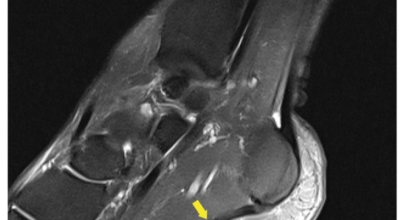

발뒤꿈치뼈 전내측 종골 결절 부위의 명확한 압통점을 찾으면 진단이 가능하고 족저 근막의 방향을 따라 발바닥에 전반적인 통증을 보이는 것을 확인할 수도 있습니다. 발가락을 발등 쪽으로 구부리거나 환자가 발뒤꿈치를 들고 서 보게 하여 통증이 증가되는 것을 보는 것이 진단에 도움됩니다. 증상이 전형적인 족저 근막염의 양상이 아니거나 적절한 치료에도 호전이 없는 경우 다른 질환의 감별 진단을 위하여 엑스레이 검사, CT, MRI, 근전도 검사 등을 시행하게 됩니다.